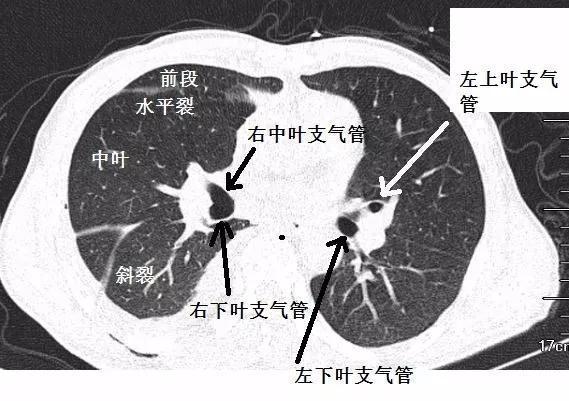

肺段ct解剖图,肺叶和肺段解剖图

肺段划分-胸部ct断层影像-肺窗(六) 解剖图片

支气管ct解剖分段图谱|ct|肺段|肺叶|心脏_网易订阅